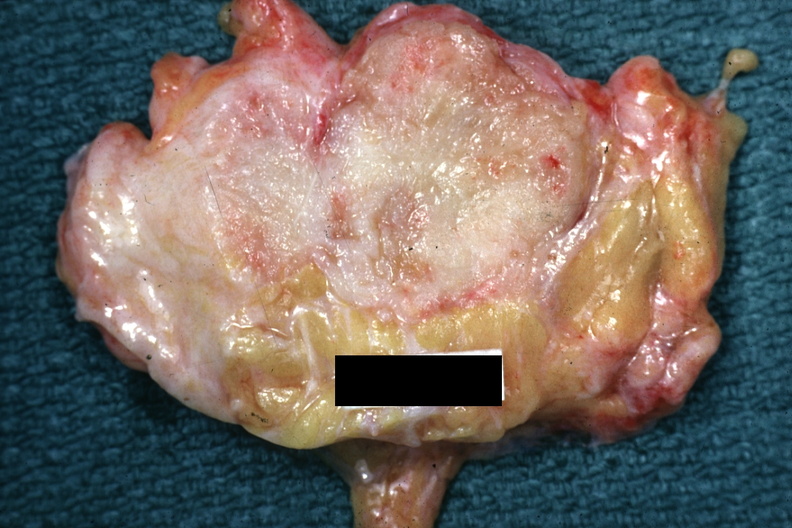

GROSS: BREAST: Adenocarcinoma: Gross good example of a breast carcinoma, slide is labeled cystosarcoma but lesion appears too small for this

- adenocarcinoma, breast, gross